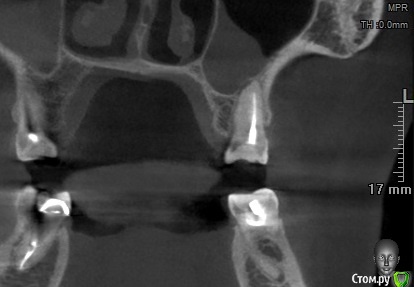

Sier10 Опубликовано 11 марта, 2021 Поделиться Опубликовано 11 марта, 2021 Здравствуйте, не стал открывать новую тему, пожалуюсь тут Прекрасная девушка, 38 лет, 26 зуб, ничего не беспокоит, на клкт периодонтит. Лечили лет 13 назад, кажется, по поводу пульпита. По плану ретрит, дальше протезирование. Удалил свш, дезобтурировал каналья, пытаюсь залезть в мб2 - тщетно. Кажется, нашел устье, 06 файл цепляет но не лезет. Смущает небное смещение устья, если это оно... Кальций. Через две недели повторное посещение.Судя по снимку мб корень имеет плоский профиль и нерегулярный мб канал. Ваше мнение, стоит ли дальше вести поиск мб2 мезиальнее? Ссылка на комментарий

St. Опубликовано 12 марта, 2021 Поделиться Опубликовано 12 марта, 2021 Да, скорее всего он медиальнее от того что искали. Возьмите твердосплав на микромотор и аккуратно уберите навес дентина от медиально щечного по медиальной стенке Ссылка на комментарий

Бардо Опубликовано 8 апреля, 2021 Поделиться Опубликовано 8 апреля, 2021 Я б навес мезиальный чуть убрал еще лонгнеком. Вы скорее всего под навес лезете файлом и он упирается в стенку 1 Ссылка на комментарий